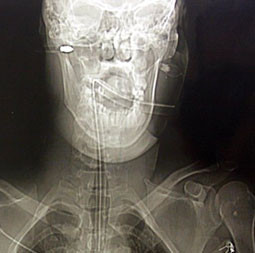

Rolanda Gedminas adlı turist olaya şahit olanların müdahaleleri ile hemen hastahaneye götürüldü. Suratında 19.2 santimlik bir delik oluşturan ok ile birlikte hemen ameliyata alınan turist uzun süren bir operasyon sonucunda başarıyla suratındaki oktan kurtuldu. Doktorların yaptığı açıklamada suratına saplanan ok 1-2 milimetre daha içeri saplansaydı olay yerinde hayatını kaybedebileceğini açıkladılar. Litvanyalı turist önlem için yoğun bakıma alınırken kendisine ok ile saldırı gerçekleştiren Rod Woollis polisin derin araştırması sonrası Grimsby Park yakınlarındaki bir barda yakalandı. Sabıkası incelenen zanlının daha önce şiddet suçundan 3.5 yıl hapis yattığı ortaya çıktı. Oklu saldırgan cinayete teşebbüsten yargılanmak üzere cezaevine gönderildi.